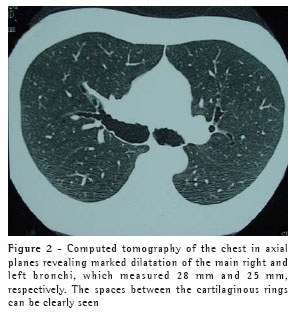

A 40-year-old black male patient was referred to the pulmonology clinic due to fatigue upon exertion and persistent dry cough three weeks after having been discharged from the hospital, where he had been admitted for treatment of pneumonia. The patient had presented, 40 days prior, a sudden onset of fever, a productive cough with a limited amount of hemoptysis, and dyspnea. He was diagnosed with pneumonia and was hospitalized, receiving intravenous cefazolin for seven days. He presented favorable evolution. The patient also reported having experienced three previous episodes of pneumonia, the first at the age of 22. The chest X-ray performed at the time of the evaluation revealed discrete areas of consolidation, of residual aspect, in the middle lobe, as well as a significant increase in the diameter of the trachea and of the main bronchi.

The patient underwent empirical treatment with a bronchodilator for two weeks, with no improvement, and then returned for a reevaluation. The cough had worsened, becoming productive. The chest X-ray taken at that time revealed new areas of consolidation in both lower lobes and in the middle lobe. There was no alteration in the vital signs, and the patient presented good general status. A ten-day course of oral erythromycin was prescribed. Over the first three days, the cough and fatigue lessened. By the end of the ten-day period, the cough had almost completely disappeared.

This treatment continued for four weeks, by which time the symptoms had been completely resolved. At that point, the patient was submitted to a computed tomography scan of the chest, which revealed that the areas of consolidation, although smaller in size, persisted in both lower lobes, and confirmed the abnormal widening of the trachea and main bronchi (Figures 1, 2 and 3). In the lower lobes, there was bilateral cylindrical bronchiectasis, which is consistent with a diagnosis of congenital tracheobronchomegaly, or Mounier-Kuhn syndrome. Pulmonary function tests revealed an increase in total lung capacity (123% of predicted) and residual volume (160% of predicted), with no other alterations. Currently, the patient remains asymptomatic, and has daily respiratory therapy sessions. Annual immunization against influenza has been recommended.

Diagnosis can usually be made by measuring the tracheal diameter, using only data from chest X-rays, in which the trachea can seen in profile and thus the diameter determined. Computed tomography of the chest, however, makes this measurement more precise. The limits are 3 cm for the transverse diameter of the trachea, and 2.4 cm and 2.3 cm for the transverse diameters of the main right and left bronchi, respectively.